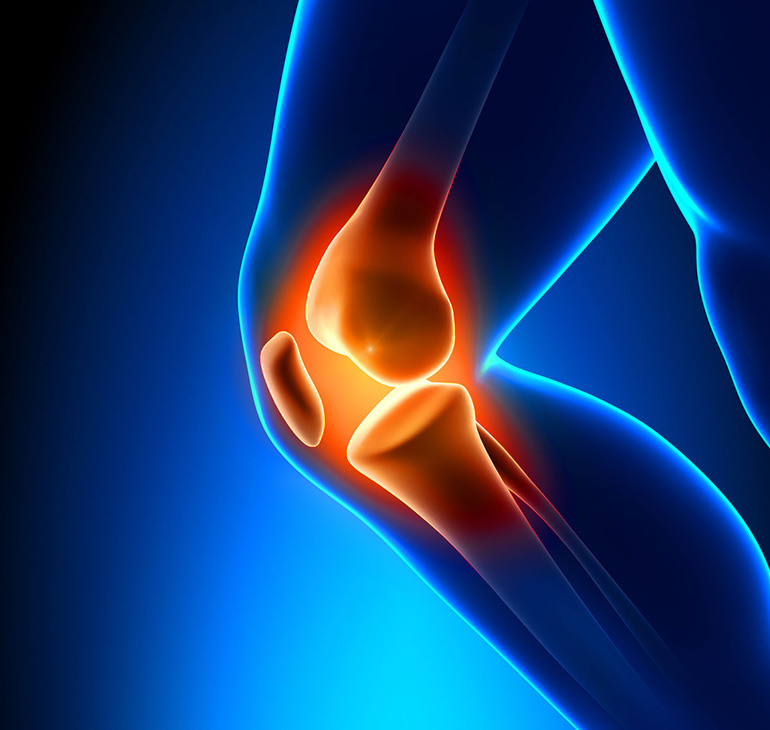

Πόνος στο γόνατο

Οι παθήσεις των αρθρώσεων είναι από τις συχνότερες παθήσεις του ανθρώπου και προκαλούν συνήθως πόνους και παραμορφώσεις. Μελέτες δείχνουν ότι 1 στους 3 ασθενείς που προσέρχονται στο ιατρείο του παθολόγου ή του γενικού ιατρού πάσχουν από κάποια νόσο των αρθρώσεων.

Μεγαλύτερη συχνότητα παρουσιάζουν οι οστεοαρθρίτιδες. Πρόκειται για χρόνιες παθήσεις των αρθρώσεων που εμφανίζονται σε μέσες ή μεγαλύτερες ηλικίες. Συνήθως προσβάλλουν μία ή δύο αρθρώσεις και εξελίσσονται με εξάρσεις και υφέσεις. Οι οστεοαρθρίτιδες στο γόνατο και τα χέρια είναι από τις συχνότερες. Αρκετά συχνές είναι και οι φλεγμονώδεις αρθροπάθειες ή αρθρίτιδες. Πρόκειται για σοβαρές παθήσεις που μπορούν να εμφανιστούν σε κάθε ηλικία. Προσβάλλουν περισσότερες από μία αρθρώσεις, συνήθως συμμετρικά, αλλά μπορεί να αφορούν και άλλα όργανα του σώματος. Τέλος, συχνές είναι και οι παθήσεις των μορίων που περιβάλλουν και κινούν την άρθρωση, δηλαδή των τενόντων, των μυών, των νεύρων κ.λπ.

Ο κόσμος τις προσδιορίζει ως πιασίματα, ψύξεις, νευροκαβαλικεύματα κ.ά., ενώ ιατρικά η γενική διάγνωση είναι ο εξωαρθρικός ρευματισμός και, ανάλογα με την συγκεκριμένη περίπτωση, τενοντίτιδα, τενοντοελυτρίτιδα, περιαρθρίτιδα, επικονδυλίτιδα κ.ά. Κάθε μία από αυτές τις παθολογίες έχει διαφορετική αντιμετώπιση, τόσο άμεση όσο και μακροπρόθεσμη.

Το ActiPatch® αποδεικνύεται ιδιαίτερα αποτελεσματικό σε κάθε μία από αυτές τις παθήσεις. Το συγκεκριμένο προϊόν σας προσφέρει 720 ώρες συνολικής λειτουργίας (on-off διακόπτης), είναι ιδιαίτερα λεπτό και ελαφρύ, συνοδεύεται από ειδική επιγονατίδα για βέλτιστη εφαρμογή της συσκευής στο γόνατο, ενώ το θεραπευτικό αποτέλεσμα εμφανίζεται άμεσα.